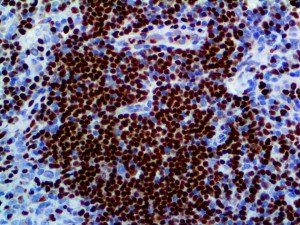

It is the ICU physician who is most likely to witness one of the deadliest manifestations of the abnormal immunological response, the cytokine storm syndrome (CSS). This response is also referred to by some as the cytokine release syndrome (CRS). CSS is characterized by continuous activation and expansion of macrophage and lymphocyte populations, which secrete large amounts of cytokines, causing the cytokine storm. This massive cytokine release is akin to hemophagocytic lymphohistiocytosis (HLH) disease, a syndrome characterized by initial unchecked and persistent activation of cytotoxic T lymphocytes and NK cells.

Clinical and laboratory manifestations of HLH include fever, enlarged liver and/or spleen, neurologic dysfunction, coagulopathy, liver dysfunction, cytopenias (i.e., low levels of erythrocytes, leukocytes, and/or platelets), hypertriglyceridemia, hyperferritinemia, hemophagocytosis, and eventually diminished NK cell activity as the immune system becomes progressively paralyzed. HLH can be familial (primary HLH) or secondary to another disease process (sHLH), such as rheumatic disease, in which it is referred to as macrophage activation syndrome (MAS, characterized by elevated ferritin).